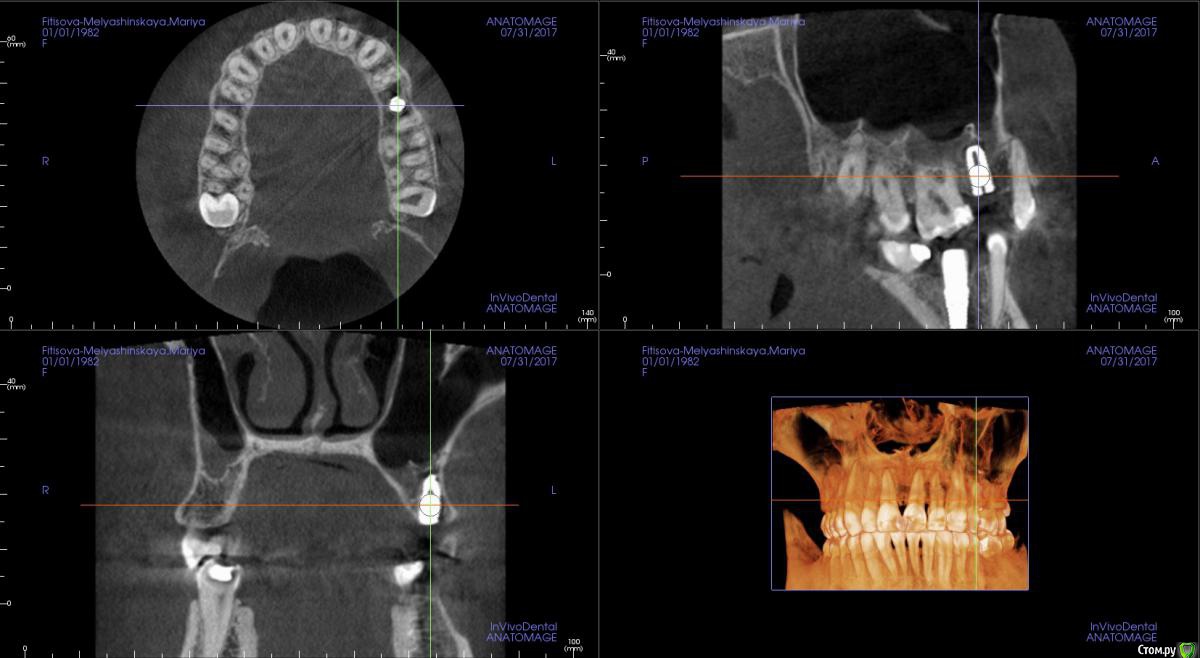

kamranchick Опубликовано 31 июля, 2017 Автор Поделиться Опубликовано 31 июля, 2017 Как то вот так получилось Ссылка на комментарий

pit Опубликовано 31 июля, 2017 Поделиться Опубликовано 31 июля, 2017 Хорошо получилось. У всех производителей можно обрезать имплант длинной 8,5 мм как минимум на 2мм) Ссылка на комментарий